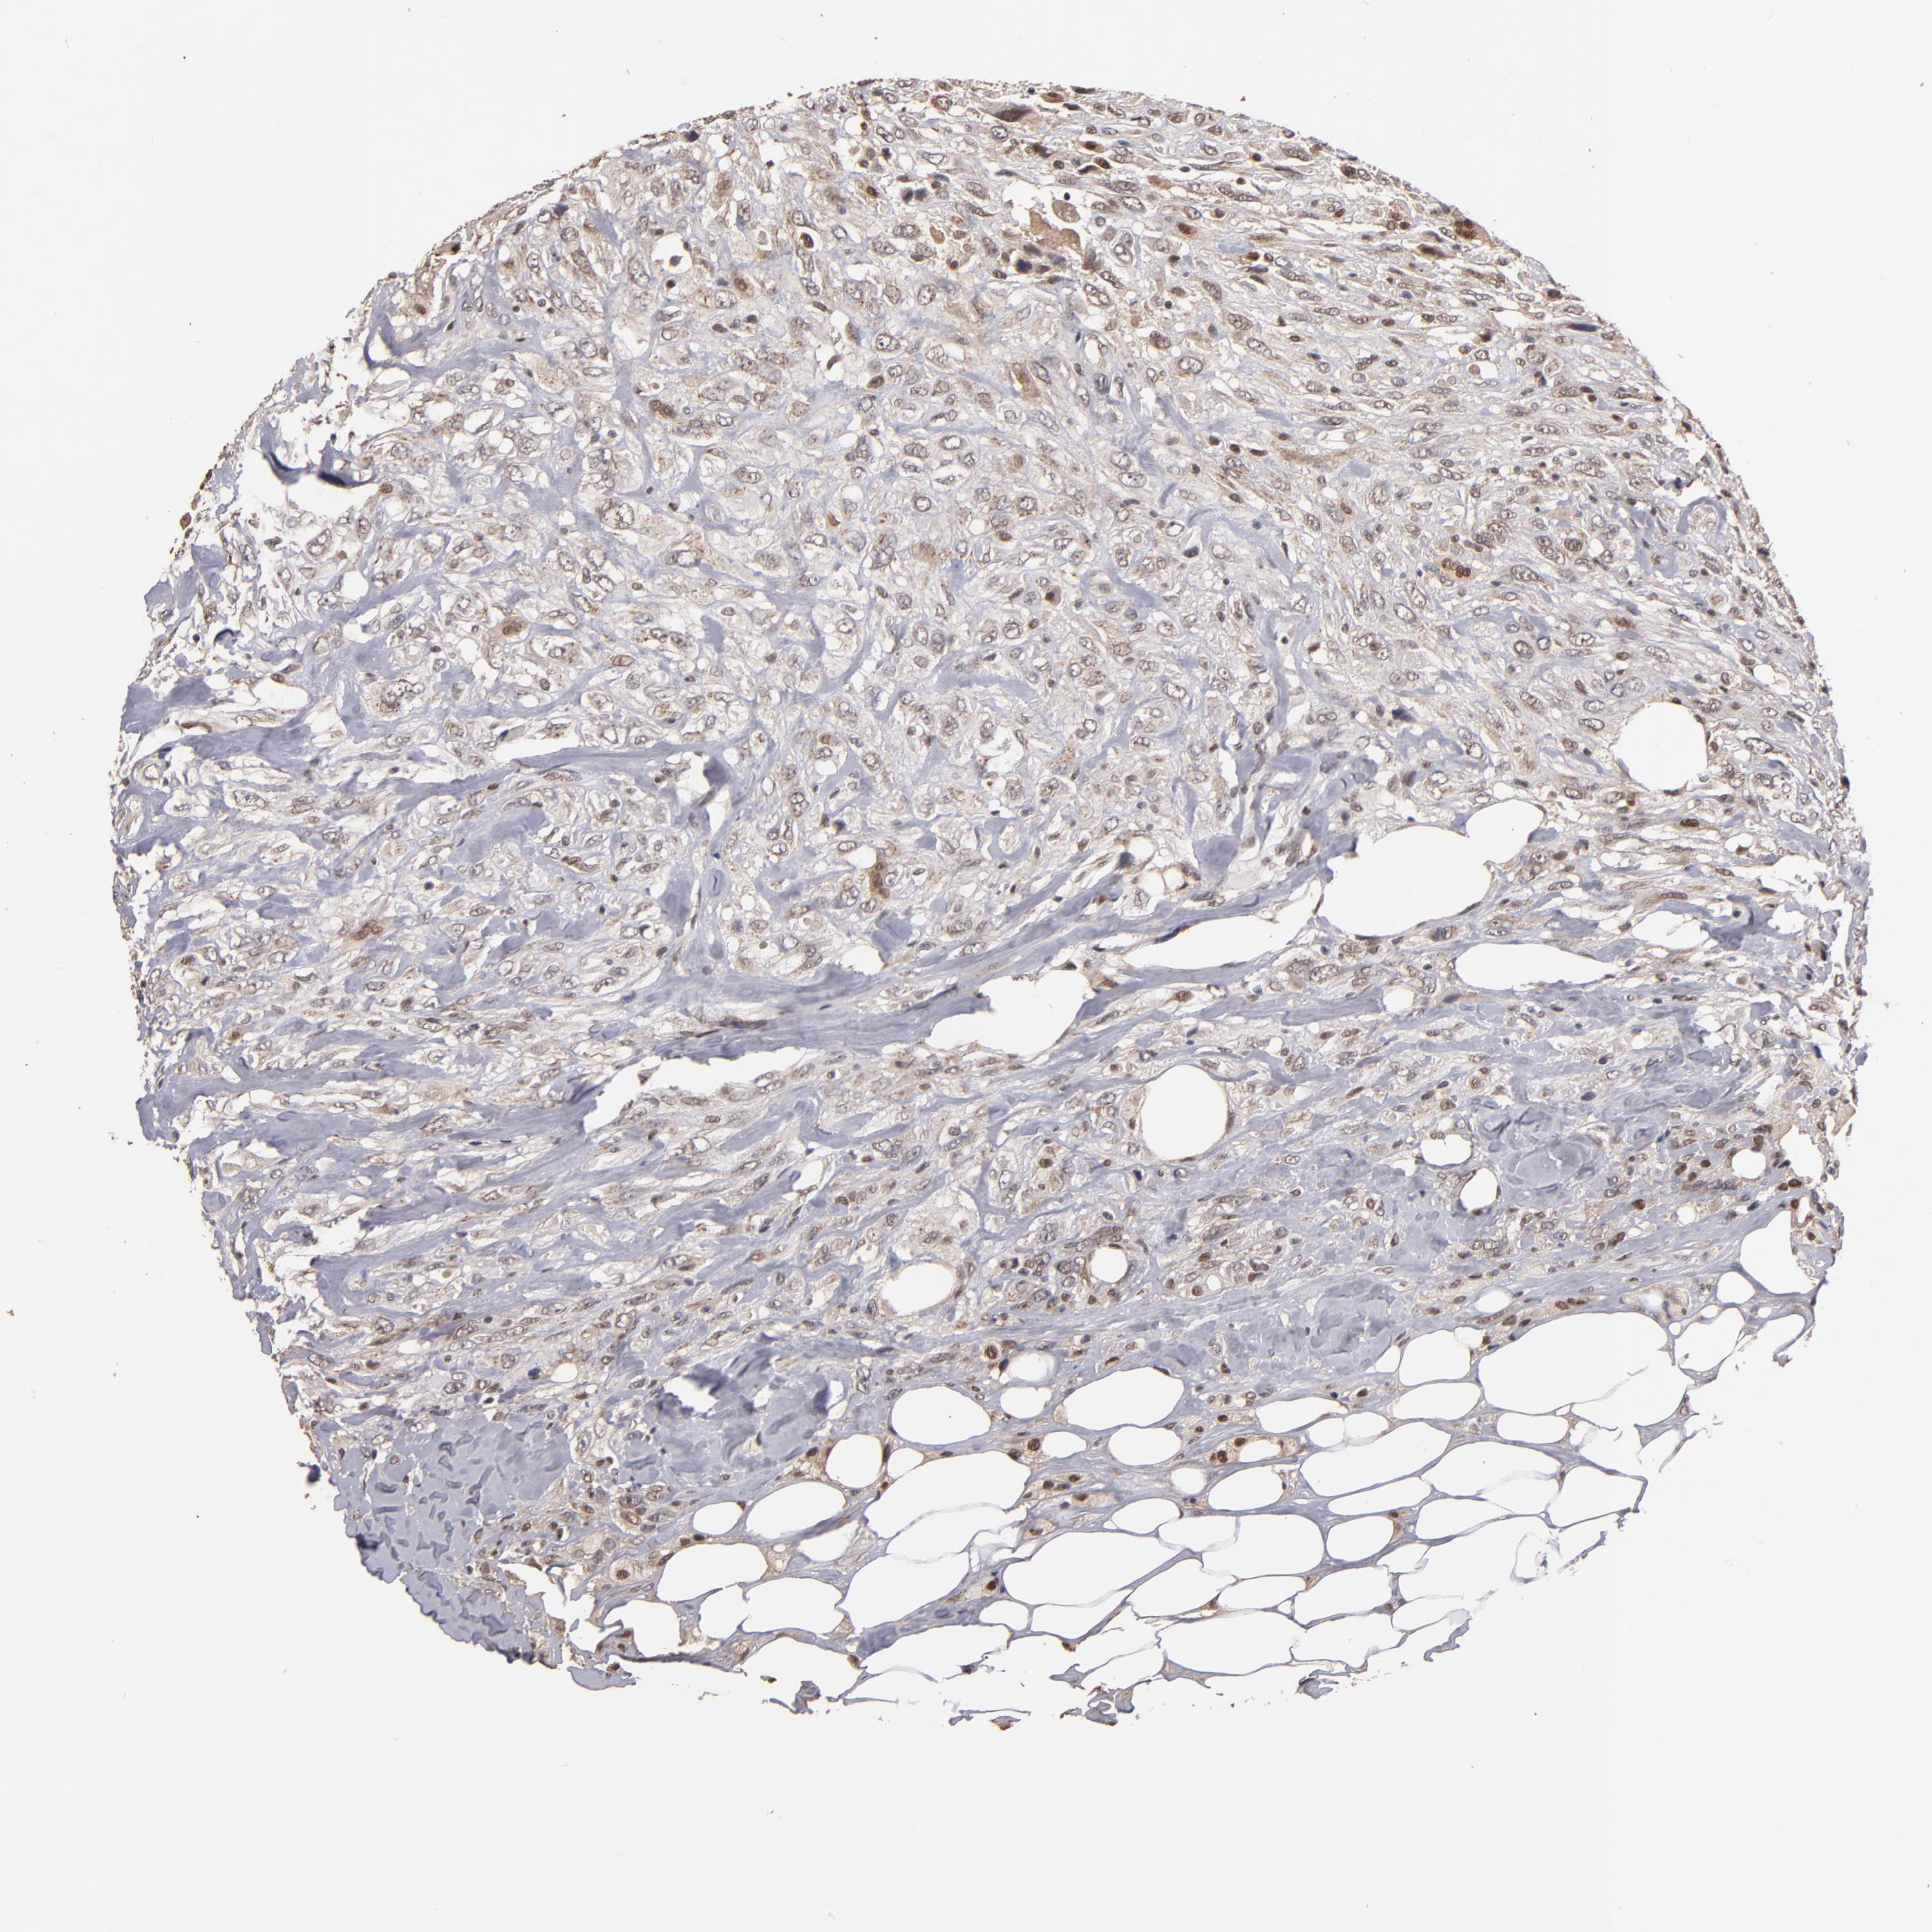

CANCER BREAST CANCER Show tissue menu

BRCA TCGA BRCA VALIDATION PROTEIN EXPRESSION

Breast cancer

Human cancer

EAPP is not prognostic in Breast Invasive Carcinoma (TCGA)